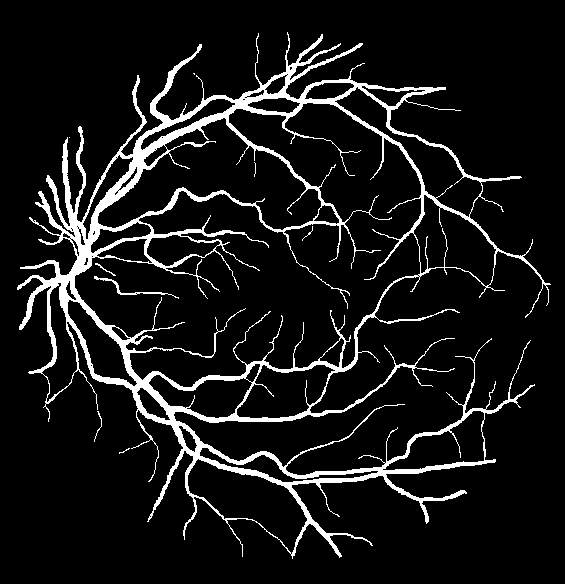

Fig. 2: An example from the DRIVE dataset. Stratification (first row, left to right): (1) input image, (2) raw mask, (3) stem mask, (4) thin mask; Segmentation Results (second row): (5) overall prediction (red are false positive area while green are false negative area), (6) raw prediction, (7) stem prediction, (8) thin prediction (of the Ngsubscript𝑁𝑔N_{g} stream)

To justify the performance of our model, we compare the 4 metrics with 8 representative previous works from all 3 open-access datasets. The comparison results presented in Table 1 show that our MP-Net model outperforms the state-of-the-art methods regarding accuracy and AUC𝐴𝑈𝐶AUC in all three datasets, which meter the practical prediction quality and the overall prediction quality independent on thresholding specifications. The AUC𝐴𝑈𝐶AUC advancement is greater in the DRIVE dataset. It’s related to the fact that the DRIVE dataset contains more thin vessels, which is the main target of our model. Specificity is also the highest in DRIVE and CHASE_DB1 while sensitivity is highest in STARE. Particularly, our method outperforms ML-UNet [2] and JL-UNet [4] which adopt a different multi-class approach to also especially tackle the thin-vessels challenge. Figure 2 shows an example of our segmentation maps on DRIVE. As can be seen, most thin vessels and boundary areas have been meticulously picked up.